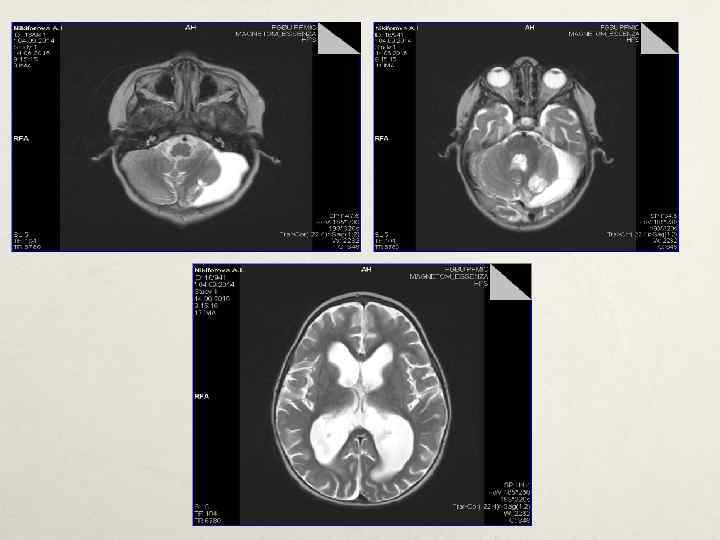

Инструментальные методы исследования 1. ЭНМГ – признаки аксоно-миелинопатии малоберцовых нервов. 2. КТ ГМ – очаговой патологии не выявлено. 3. ЭЭГ – диффузные изменения бэа мозга, диффузная бэта-активность на ЭЭГ. 4. МРТ ГМ - признаки множественных очаговых изменений лобных долей. Признаки перевентрикулярной лейкопатии затылочных долей. Умеренная выраженная смешанная гидроцефалия заместительного характера. 5. МРТ ПКО позвоночника – МРТ – признаков очаговых и диффузных изменений нижнегрудного и пояснично-крестцового отделов позвоночника и спинного мозга не выявлено. 6. ЭКГ – ритм синусовый с СС 150 в минуту. Нормограмма. 7. ЭХОКГ – диагональная трабекула полости ЛЖ, гипертрофия ЗСЛЖ. 8. Хромосомный микроматричный анализ – хромосомного дисбаланса не обнаружено.